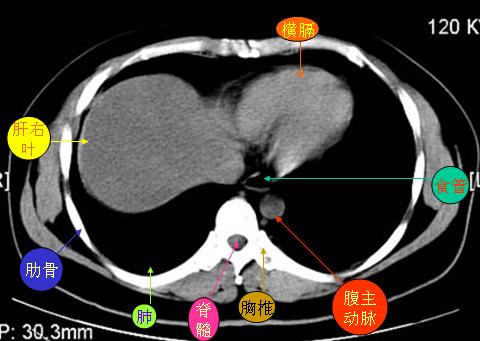

腹部ct解剖与基本病变